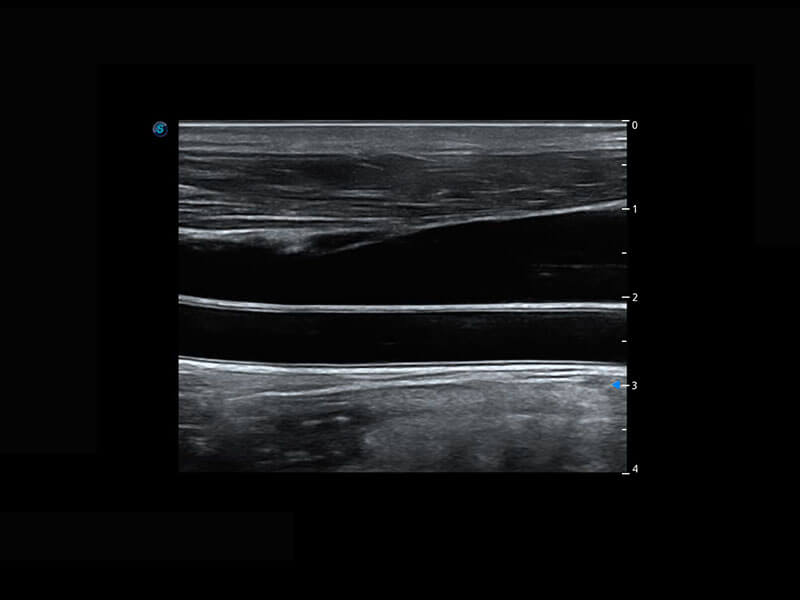

P60搭載寬頻帶線陣探頭、寬景成像、彈性成像技術(shù),為您提供乳腺應(yīng)用方案。P60支持高頻相控陣探頭、線陣探頭、腹部高頻探頭、腹部微凸探頭等,豐富的探頭群搭載敏感的彩色血流成像,適用于新生兒多種臟器檢測(cè)要求,滿足新生兒篩查需求。

乳腺導(dǎo)管癌

乳腺癌顯微血流